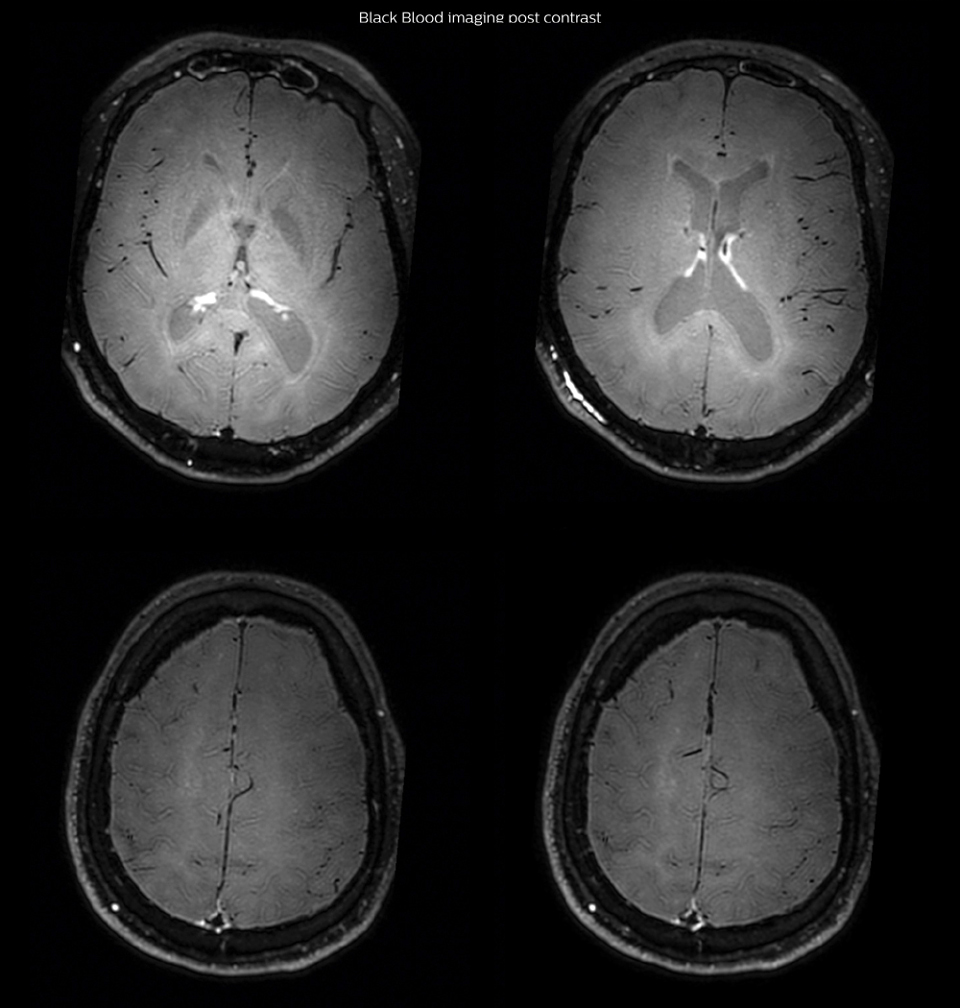

had, such as glucose intolerance, arterial hypertension and hypocholesteremia, his lesions could be atherosclerotic lesions or vasculitis, conditions which require different treatment. Especially in this patient with HIV infection causing the vasculitis, treatment of the two conditions is different. The results of MRI with Black Blood imaging, helped to choose the preferred treatment for this patient, which was based on antiviral medication rather than an antiaggregant or anticoagulation treatment which is usually given to patients with risk of ischemia based on atherosclerotic lesions. One month after beginning the antiviral treatment, the same MRI examination was repeated and again 8 months after the beginning of treatment. On follow-up images, we see the enhancements have almost disappeared. So in case of this patient, the MRI exam with Black Blood imaging helped us to give the patient the appropriate treatment and also allowed us to noninvasively confirm the treatment response.

After one month of treatment, post-contrast Black Blood images at the exact same levels as in the figure above show disappearance of the vessel wall enhancements which were seen on the previous examination.